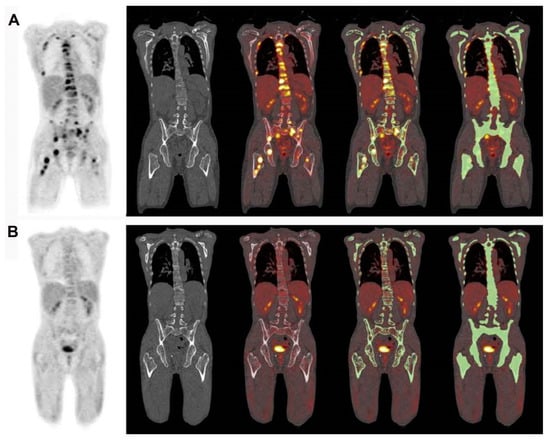

Evaluating the response to treatment is a significant area where [18F]FDG PET/CT might offer greater utility compared to conventional imaging methods [23] (Figure 4 and Figure 5). By analyzing the metabolic behavior in areas with clonal plasma cell growth, [18F]FDG PET/CT can precisely gauge and quantitatively measure alterations in cancer cell activity following therapeutic interventions [24,25,26,27,28,29]. Furthermore, there is a robust correlation between negative [18F]FDG PET/CT results and a highly positive response to treatment in myeloma patients [20].

Figure 4.

This figure presents the case of a 39-year-old patient with symptomatic multiple myeloma (MM) who was being prepared for high-dose therapy (HDT) and autologous stem cell transplantation (ASCT). This patient underwent an [18F]FDG PET/CT scan both before and after treatment. The maximum intensity projection (MIP) of the [18F]FDG PET/CT scan before treatment (A) revealed a combination of intense, widespread uptake in the axial skeleton and multiple focal bone marrow lesions in locations such as the sternum, ribs, humerus, scapula, and femur (indicated by arrows). The follow-up [18F]FDG PET/CT MIP after HDT and ASCT (B) demonstrated a complete remission of both the diffuse bone marrow uptake and the focal MM lesions. Figure 2, PMID: 31905752, PMCID: PMC6982887, OPEN ACCESS.

Figure 5.

This figure is displaying the baseline (A,B) and follow-up (C,D) [18F]FDG PET images of a patient with MM before high-dose chemotherapy and 2 months post-treatment. The [18F]FDG uptake by the lesions was quantified using an adaptive thresholding algorithm. The image was sourced from PMID: 31084773 (Figure 3), and permission was granted for its use.